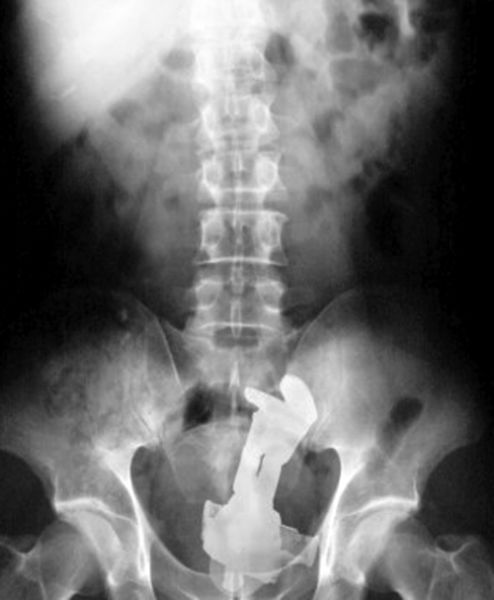

Bottle of beer